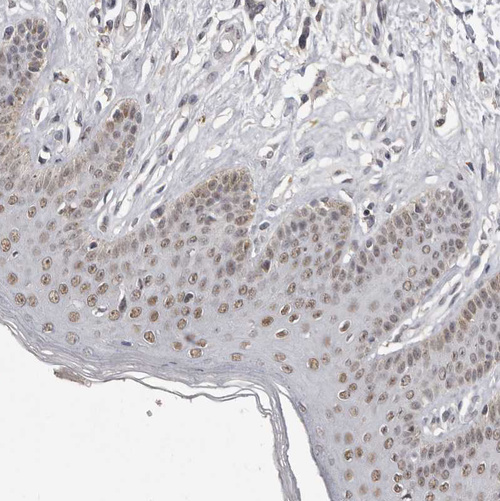

Immunohistochemical staining of human Testis shows moderate nuclear positivity in cells in seminiferous ducts and leydig cells.